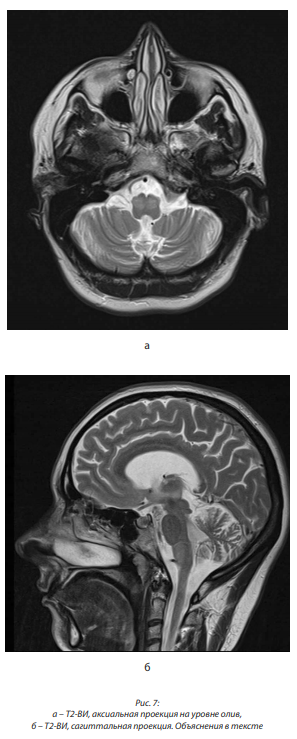

В июне 2017 г. выполнена МРТ головного мозга, заключение: МР-картина гипертрофической оливарной дегенерации (в продолговатом мозге с обеих сторон выявляются симметричные участки измененного МР-сигнала, гиперинтенсивные на Т2 ВИ и FLAIR размерами 15×7 мм справа и 14×7 мм слева, с четкими контурами, без перифокального отека; продолговатый мозг на этом уровне слегка вздут; боковые и III желудочки расширены, симметричны; субарахноидальные пространства конвекса и базальные цистерны не расширены) (рис. 7, а, б).